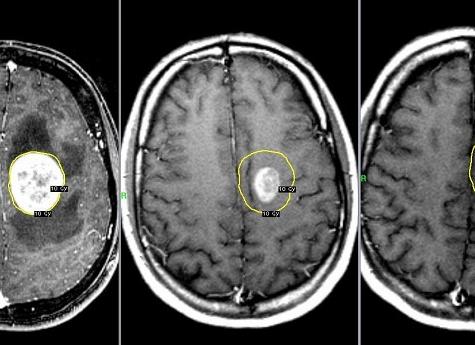

• Злокачественные опухоли. При контрастном усилении лучше видны границы опухоли и ее структура.

• Поиск метастазов в мозге. Контрастное усиление повышает вероятность выявления распространения опухолевых клеток из места возникновения (первичной опухоли) в другие отделы и органы организма пациента.

С помощью магнитно-резонансной томографии получают отчетливые изображения всех структур головного мозга, включая серое и белое вещество, подкорковые образования, ствол, гипофиз. Также на снимках хорошо видна церебральная сосудистая система (артерии, вены, венозные синусы). Выявляет МРТ мозга и патологические изменения в ликворопроводящей системе, менингеальных оболочках. При необходимости дополнительно оценивается состояние орбит и придаточных пазух носа.

Видно на МРТ мозга как очаговые, так и диффузные изменениях в структуре нервной ткани. На полученных во время сканирования снимках отображаются воспалительные, опухолевые или деструктивные изменения. Незаменим метод и при травматических повреждениях головы различной степени тяжести. В этом случае нейрохирурги часто рекомендуют проведение МРТ мозга, что выявляет зоны ушиба, гематомы, внутримозговые кровоизлияния.

• новообразования доброкачественного и злокачественного характера (глиобластомы, менингиомы, аденомы гипофиза, кисты и др.);

МР-томография предоставляет возможность получать изображения всех внутричерепных структур с максимальной их детализацией. Методика выявляет очаговые изменения в тканях размерами менее миллиметра. Это позволяет диагностировать патологические состояния еще на начальных стадиях развития, когда лечение дает максимальный эффект. Особенно это актуально в случае злокачественных опухолей, новообразований гипофиза. А некоторые заболевания, такие как, например, рассеянный энцефаломиелит, диагностируют только при помощи МРТ.

Некоторым больным МРТ головного мозга проводят с дополнительным введением контрастирующего препарата. Такое исследование необходимо для дифференциальной диагностики и уточнения характера выявленных очаговых изменений, особенно при подозрении на злокачественность процесса. Для процедуры используют контрастные препараты, содержащие гадолиний (Магневист, Гадовист). Контрастирующие препараты обычно хорошо переносятся пациентами и редко вызывают побочные реакции.